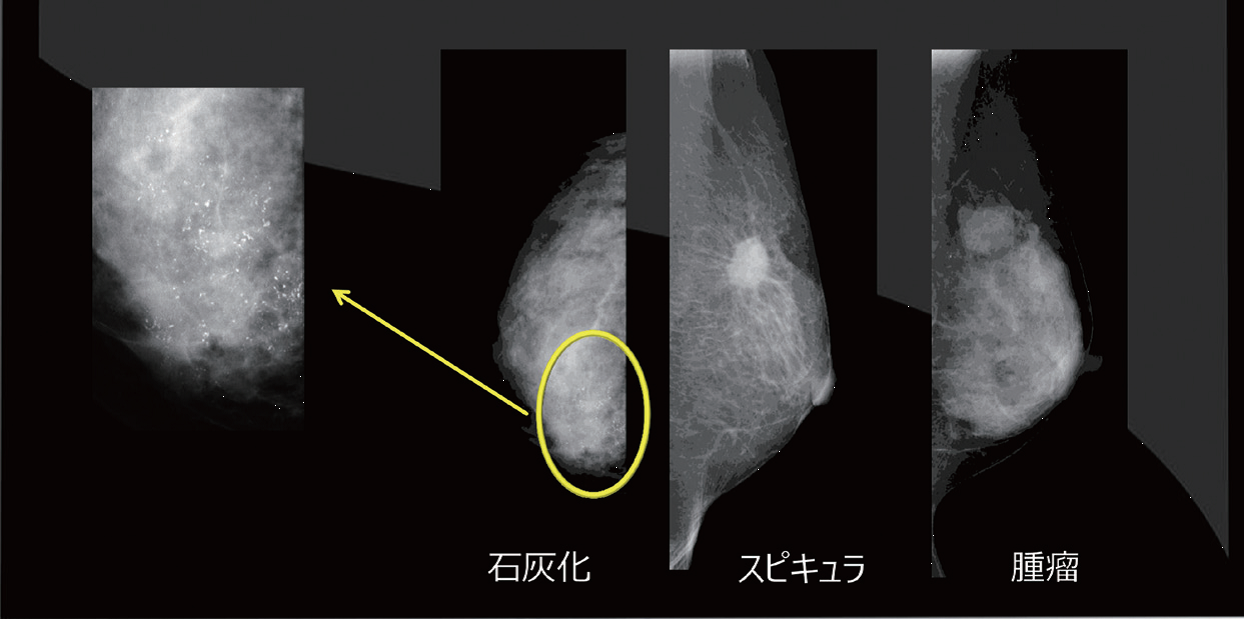

乳癌の発見には石灰化がヒントになることがしばしばある。石灰化の大きさは約50 〜200マイクロメートルで、そのような微小な石灰化を描出するには、高い空間分解能・高い濃度分解能が必要である。しかし、モニタの表現能はフィルムよりコントラスト比や解像度の点で劣る。そのため、原画像の持つ性能を十分に発揮・利用できる機能を有するモニタを最適な表示環境で用いることが重要となる。

モニタの品質管理の重要性

モニタの日常管理では、まずモニタ画面の清掃・周囲光の確認を行う。続いて全体評価試験で、TG18-QCテストパターンでモニタ全体の画質評価を行う(図1)。次に、各施設で準備した判定用臨床画像で、判定箇所の見え方を確認する。当院では石灰化、スピキュラ、腫瘤の3種類の画像で行っている(図2)。さらに、ファントム撮影で、エックス線発生から画像観察までのシステム全体における画質および線量に関する経時的変化の確認をする。

その結果、輝度の低下によるファントム画像の点数の変化は大きくなかったが、一部の石灰化や腫瘤がぼけて正しく認識できない恐れがあった。また、高輝度領域では白い部分の粒状性が悪くなり、高濃度乳腺で視認性が低下する可能性が考えられた。一部の症例においてはカテゴリー判定を見誤る可能性があるため、モニタ管理の重要性が示唆された。